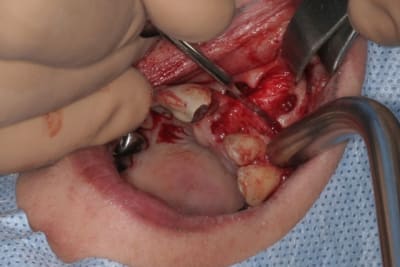

un autre cas EII MCI sur 11/21...mais en photos (j'ai aussi la vidéo, faut que je la passe sur youtube)

1 t869zn - Eugenol

2 v0ltek - Eugenol

3 rz5ncz - Eugenol

4 k166af - Eugenol